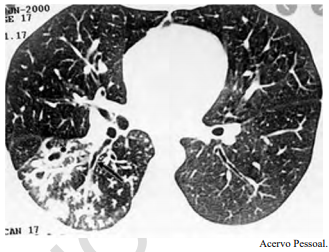

Um adolescente de 17 anos de idade procura atendimento em função de tosse vespertina, febre e hemoptise em pequena quantidade. Refere sudorese noturna e perda de peso. A tomografia de tórax apresenta nódulos centrolobulares com padrão de árvore em brotamento, além de pequenas cavitações espessas e de paredes irregulares, bem como brônquios espessados em segmento posterior do lobo inferior direito, conforme a imagem a seguir.

Tendo em vista esse caso clínico, a imagem apresentada e os conhecimentos médicos correlatos, julgue o item a seguir.

Está indicada a coleta de BAAR e PCR para Mycobacterium tuberculosis no escarro. Caso dê negativo, pode ser realizada a coleta de lavado brônquico para diagnóstico.